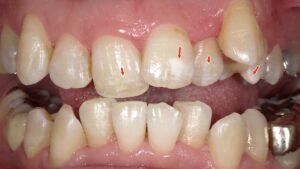

この画像は、C4(う蝕症第4度)=重度の虫歯の状態を示しています。

赤い矢印の部分がすべて、**歯冠がほとんど崩壊し、歯根のみが残存している状態(残根状態)**です。

📚赤矢印=保存可能、青矢印=抜歯妥当

- 赤矢印で示された歯は、保存治療が可能と診断。

- 青矢印で示された歯は、抜歯が妥当と診断。

- ※見た目だけでなく、レントゲン(X線検査)結果も踏まえた総合判断によるものです。

✨虫歯C4症例1|各歯の診断結果(視診+レントゲン診断)

🔹保存可能と判断された歯

- 右上1番(上顎中切歯)

- 左上1番(上顎中切歯)

- 右上7番(上顎第二大臼歯)

✅ 視診およびレントゲン検査により、歯根・周囲組織に保存可能な状態が確認された。

🔹抜歯と判断された歯

- 左上2番(上顎側切歯)

- 左上6番(上顎第一大臼歯)

- 右上6番(上顎第一大臼歯)

⚡ 視診とレントゲン結果から、歯根破折・重度感染・歯槽骨吸収が認められたため、保存は困難と判断。